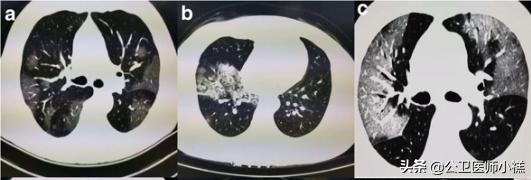

早期CT肺部影像学

在早期胸部影像学改变为肺低玻璃阴影

毛玻璃样阴影

肺实变和结节

肺结节

中心结节周围毛玻璃样改变

中心结节、周围毛玻璃样改变

根据感染的不同程度累积一个或多个肺叶